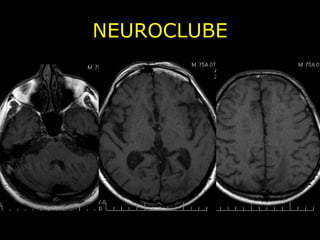

NEUROCLUBE Angiopatia Amilóide Cerebral - Depósito de proteína b-amilóide cortical, subcortical e leptomeninge; - Hemorragia cerebral em normotenso; - Assintomático e sintomático;

NEUROCLUBE CASO 2